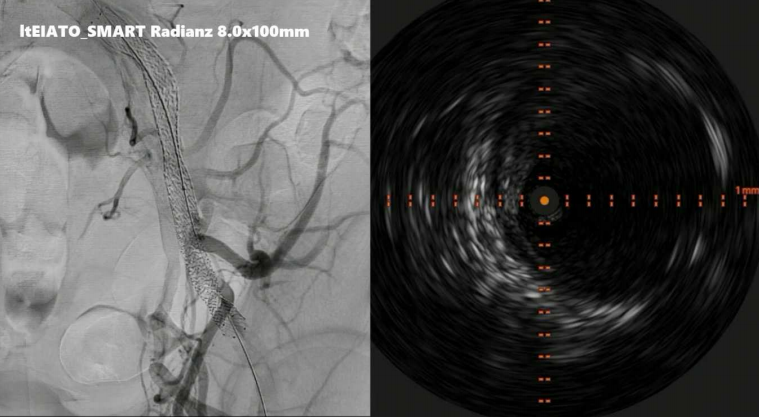

病例二:左侧髂外动脉完全闭塞

术者采用IVUS引导下精准导丝通过。目前,支架已有适用于经桡动脉介入的长鞘版本,因此可经桡动脉置入覆膜支架,通过造影和IVUS进行评估,可见支架植入后即刻效果理想。

动脉长鞘怎么置入桡胜一筹丨原口拓也:经桡动脉入路在下肢动脉疾病腔内治疗中的优势——RADIANZ应用经验_https://www.jmylbn.com_新闻资讯_第33张